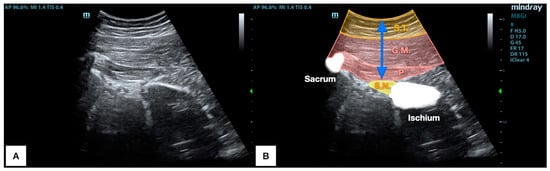

2.5. Ultrasound Imaging Procedure: Piriformis Deep Limit Calculation